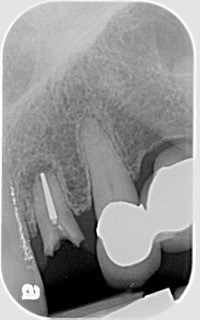

Both Caroline’s and Karen’s lateral incisors were removed, and immediate implants were placed. Although the implant surgeons were different, they were both long-time members of my interdisciplinary team and had significant implant placement experience. Both implants were torqued to 50 Ncm at the time of placement. Provisionals were then placed by me that same day.

This intimacy is referred to as the bone-to-implant contact. It is a function of both the implant length and diameter (BIC). This intimate contact provides the primary stability of the implant. Acceptable stability is verified through the torque testing at the time of placement. 50 Ncm or greater torque is considered acceptable for immediate implant loading.

Lastly, implant diameter and length are significant considerations in implant stability. The longer the implant, the greater the surgeon’s ability to engage bone and achieve primary stability, especially in an immediate extraction — immediate placement scenario. Wider implants provide greater BIC for healing, but implant stability and the emergence profiles of the abutment are limitations for a “wider is better” concept. Ultimately, force management is the key to successful implant integration and longevity!